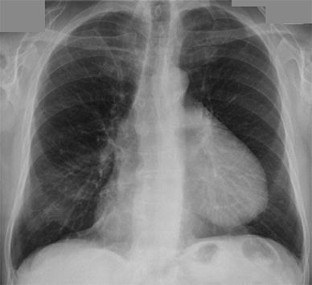

Fig. 1